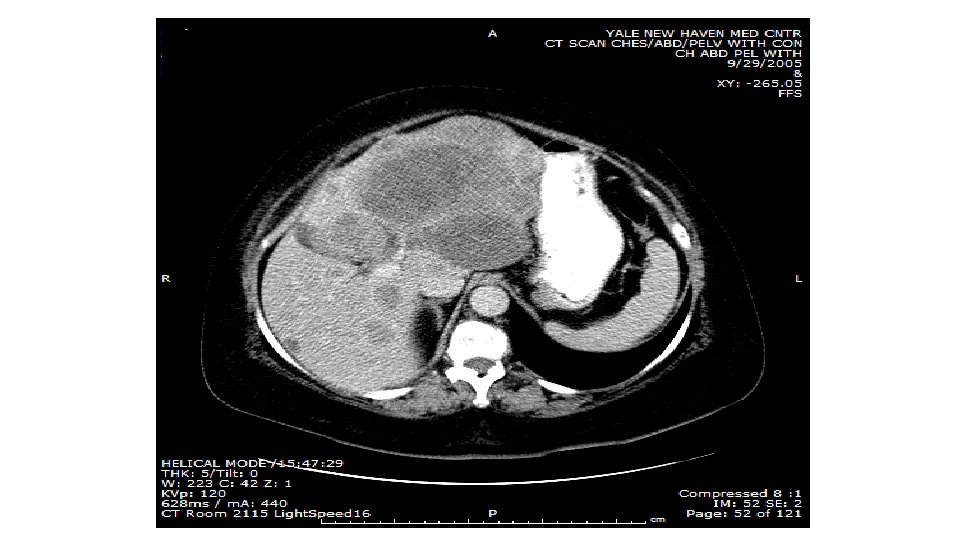

Il-2 Induced Regression of Melanoma Liver Metastases 6 -24 -05 11 -23 -05 Persistent/progressing disease in spleen, SQ buttock, and lung removed; NED x 7 years